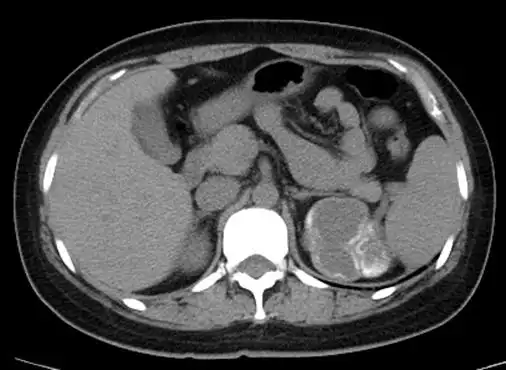

肾结核_钙化